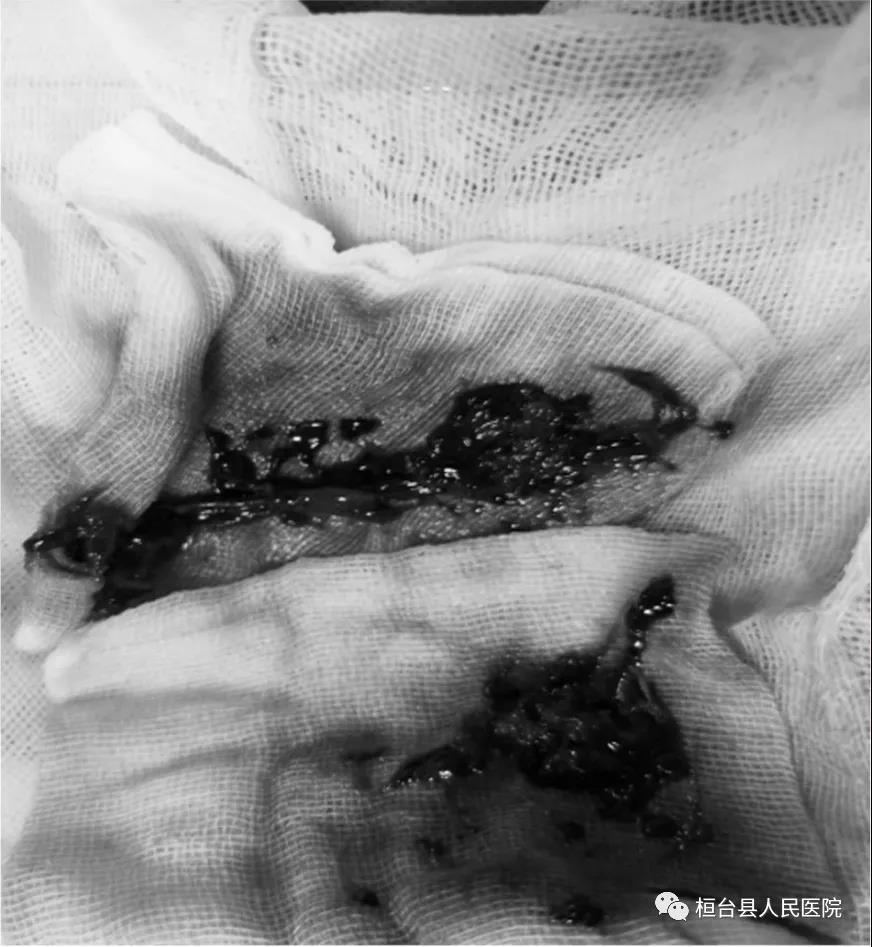

介入血管外科为患者实施下腔静脉滤器置入+取栓+置管溶栓术。术中造影示左下肢股浅静脉、腘静脉完全闭塞,随即穿刺腘静脉行介入血栓抽吸,并留置溶栓导管继续溶栓,大量暗红色血栓被取出,患者瘀堵的股浅静脉及时开通。术后患者恢复良好,下肢肿胀症状明显减轻,术后第二天可正常下地活动。 取出的血栓